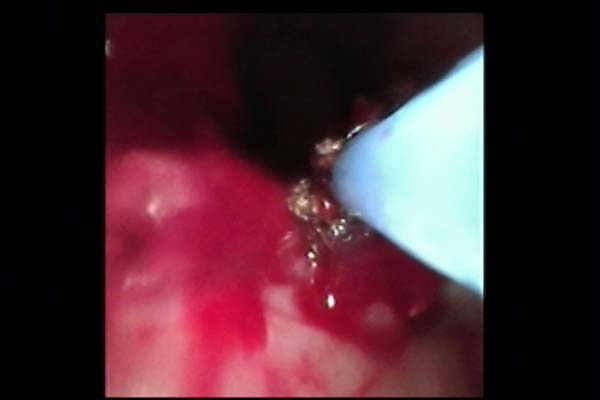

手术中,胸外科团队采用多技术联合操作策略:首先通过常规电子支气管镜完成病变探查与定位,随后置入硬支气管镜建立稳定操作通道,保障术中通气安全。针对气道内增生组织,团队交替使用氩气刀进行精准切除,并应用冷冻治疗仪对残余病灶进行消融与止血。最后在硬镜支撑与细支气管镜引导下,完整取出原有气管支架,未对气道黏膜造成附加损伤。

图2 术中氩气刀治疗

图3 术中冷冻治疗

图4气道肿物清除术后图